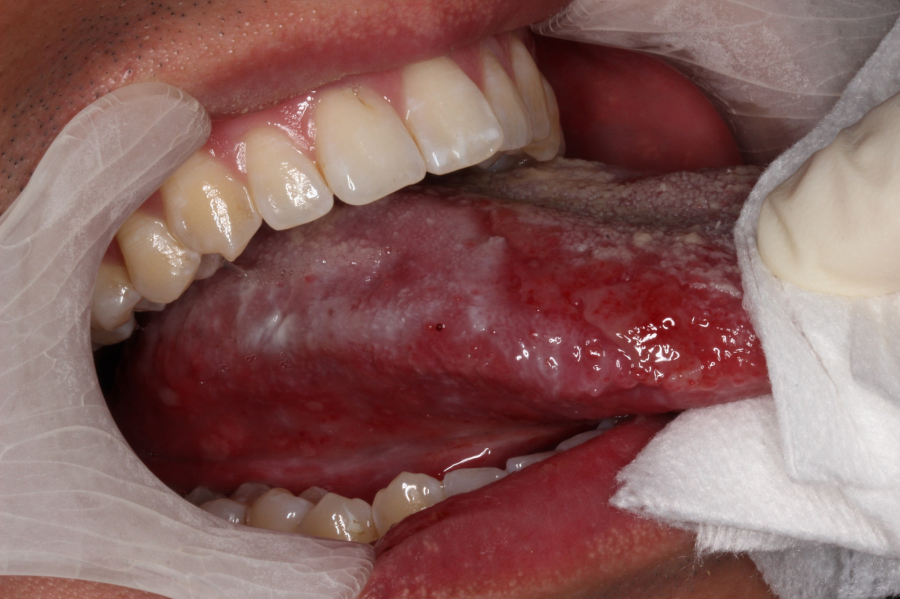

口腔癌初起的表徵很多時是口腔内一些白斑,臨床診斷為口腔白斑病(oral leukoplakia OL) 和口腔類扁平苔蘚黏膜炎(oral lichenoid mucositis OLM)。這些白斑可能在出現一段長時間後才被確診口腔癌,所以能儘早發現並持續監察,防止它們惡化發展至為重要。